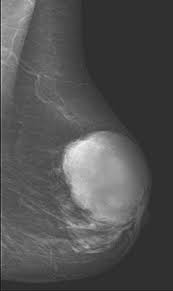

- Phyllodes tumors:Are true fibroepithelial neoplasms:With both epithelial and stromal components

- They represent less than 1% of all breast tumors:Most commonly occurring in women in their 50sThey are rapidly growing tumors:But are usually well-defined / circumscribed:Often appear as distinct masses:Indistinguishable from fibroadenomas on mammography and ultrasound